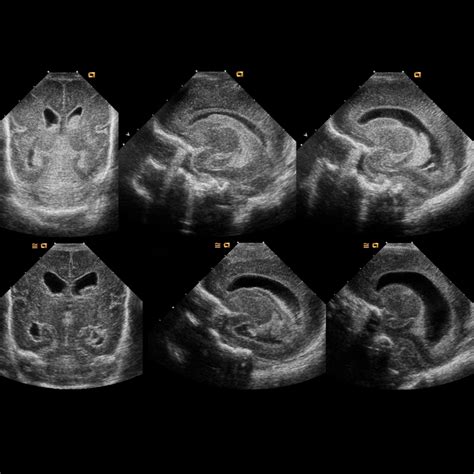

• Ultrasound (Sonography): Preferred for its ability to produce high-quality images without any radiation, making it ideal for abdominal or soft-tissue issues.

Ultrasound None Abdominal organs, neonatal brain, appendicitis